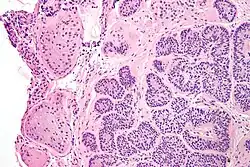

| Micrograph of a Sertoli cell nodule. H&E stain. | |

Sertoli cell nodules are unencapsulated nodules that consist of:[2][3][4]

- cells arranged in well-formed tubules (that vaguely resemble immature Sertoli cells), with

- bland hyperchromatic oval/round nuclei that are stratified, and

- may contain eosinophilic (hyaline) blob in lumen (centre).